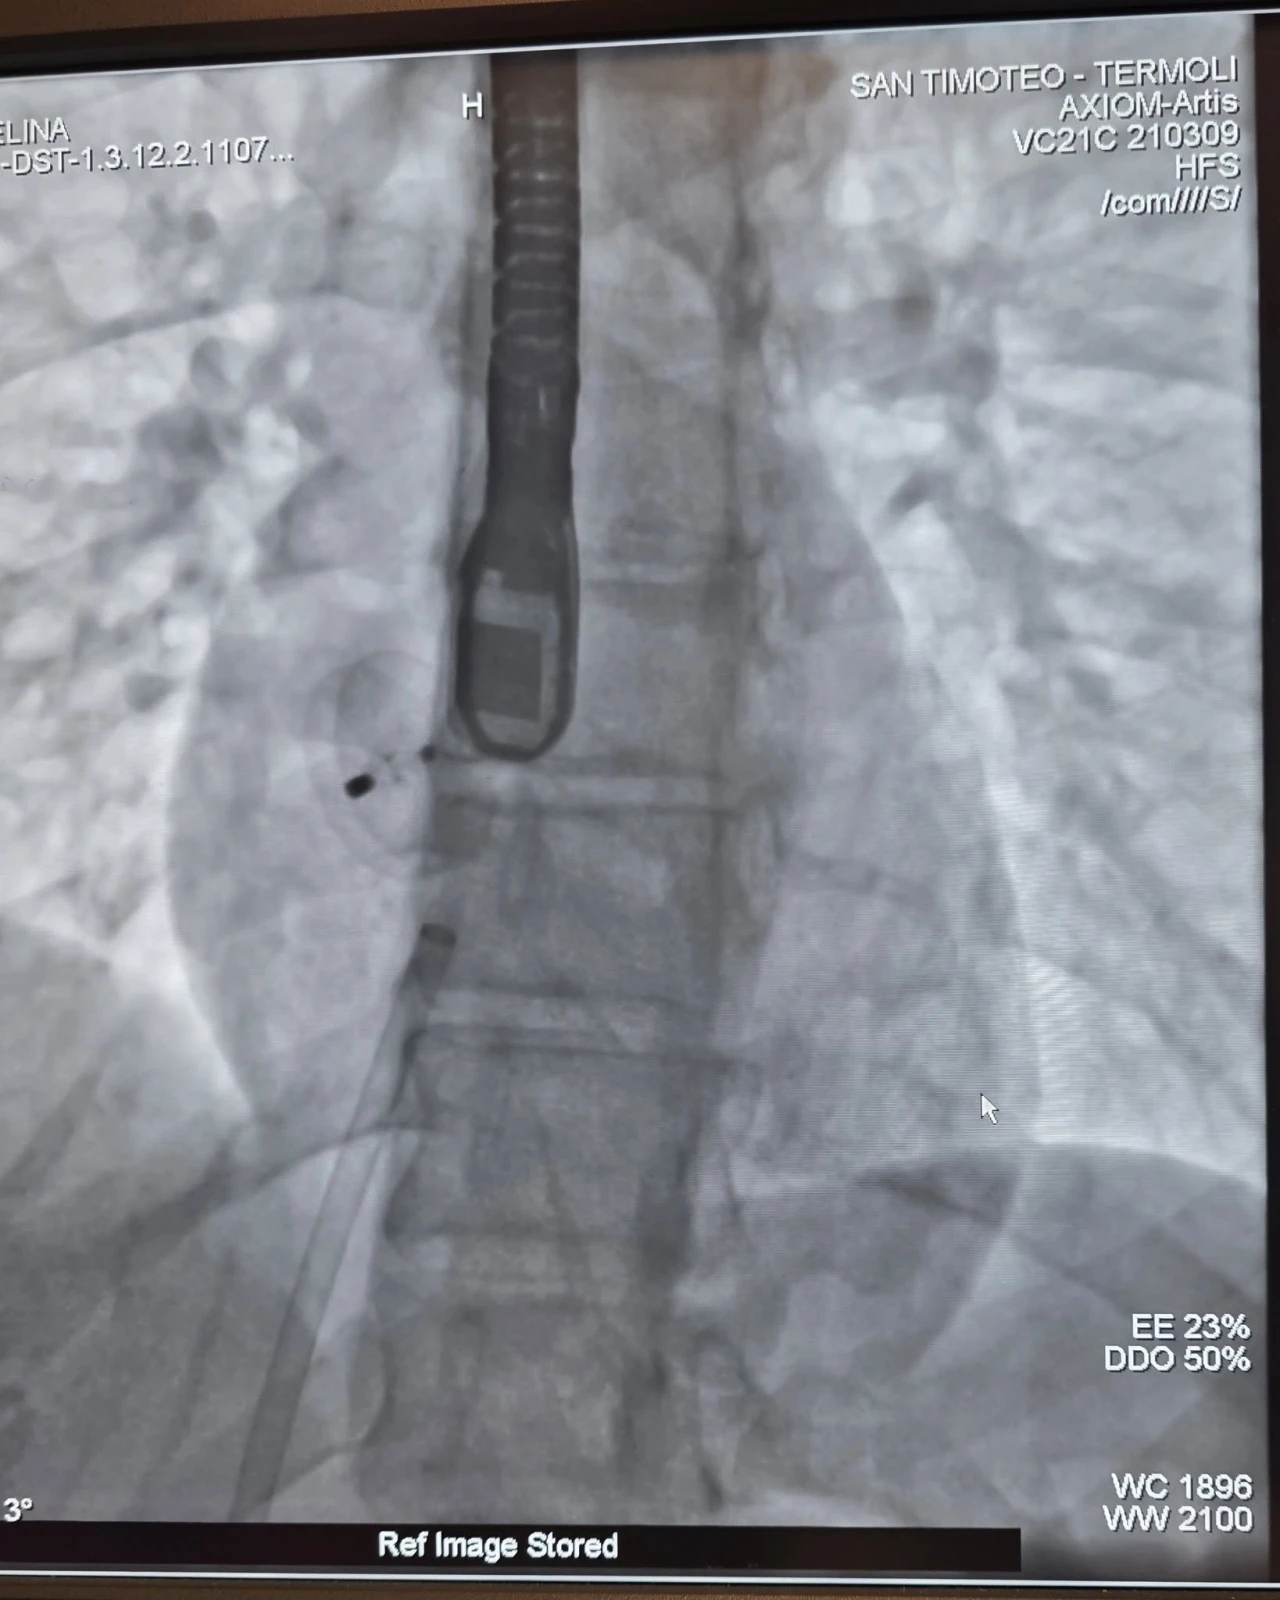

Procedure interventistiche di rilievo anche al P.O. San Timoteo di Termoli dove, in questi giorni, sono state effettuate due chiusure per via percutanea di Forami Ovali Pervi (PFO) in due giovani pazienti con precedenti episodi di ischemia cerebrale. Si tratta di interventi mini-invasivi che mirano a chiudere una comunicazione anomala tra i due atri del cuore, spesso identificata come un'apertura residua del forame ovale presente nel periodo fetale. Si eseguono mediante l'introduzione di un dispositivo, simile a un ombrellino, attraverso un catetere, generalmente introdotto attraverso la vena femorale.